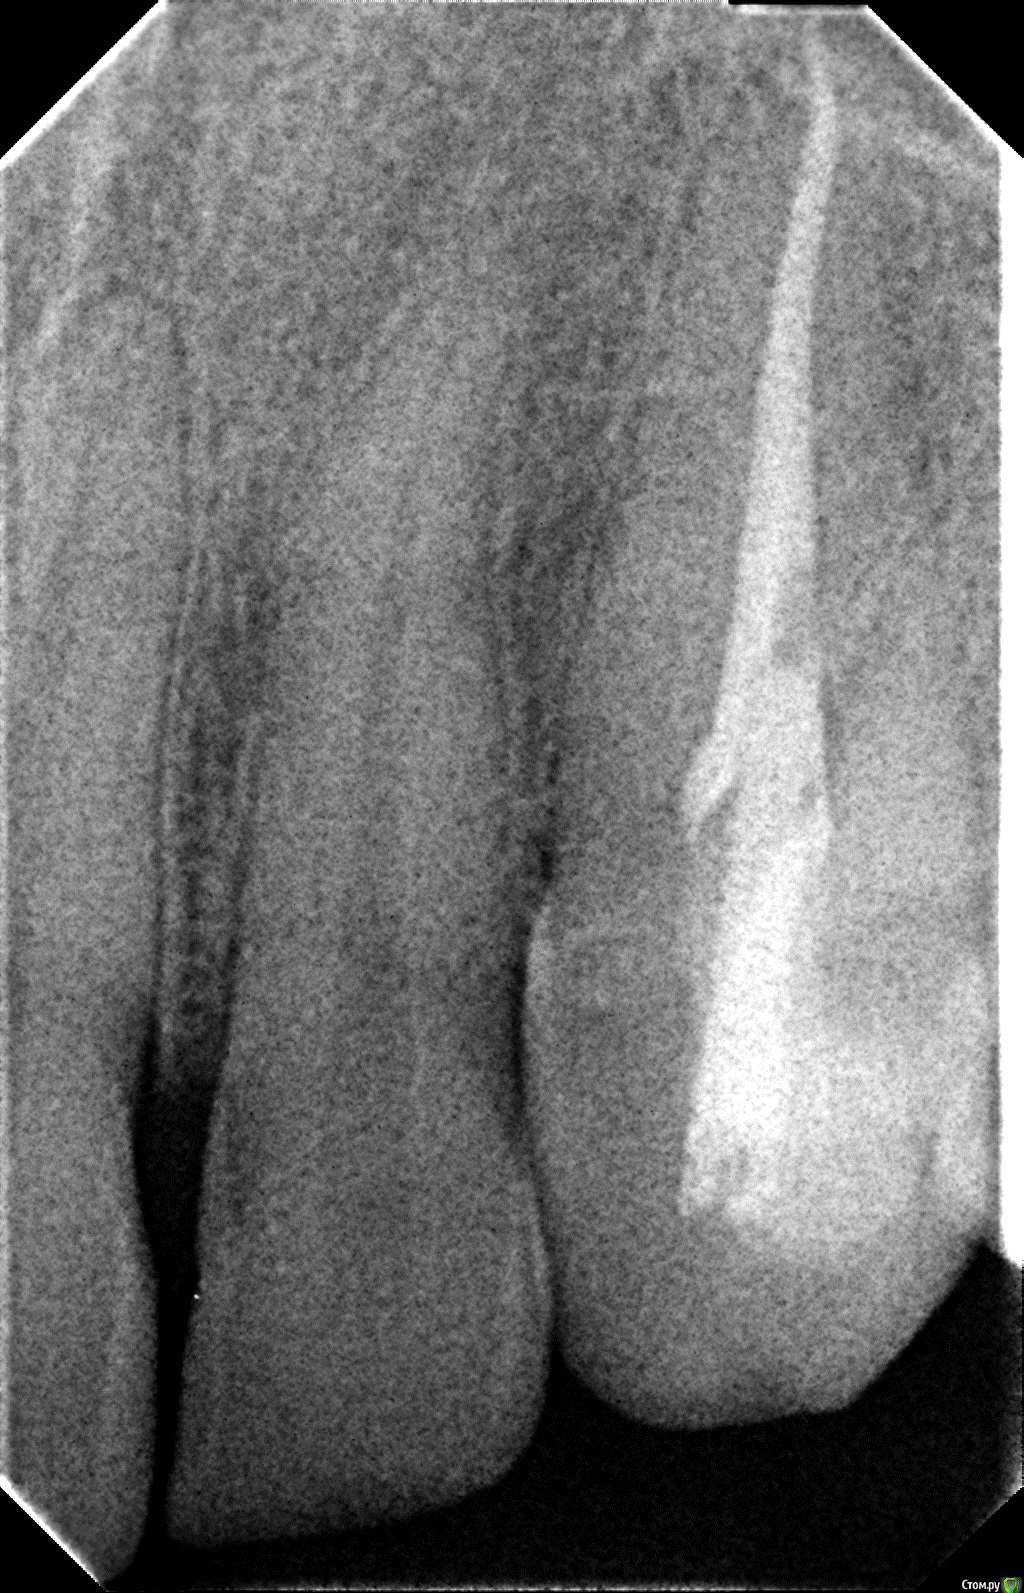

Jorus Опубликовано 27 октября, 2015 Поделиться Опубликовано 27 октября, 2015 (изменено) Добрый вечер уважаемые! Хочу спросить совета.1.Неделю назад был установлен титановый штифт (Radix Anker Standart)(желтый) на 23 зуб (клык), стоматолог не предупредила меня.Сам штифт видно из под пломбы с внутренней стороны. На кончике языка который соприкасается со штифтом есть постоянное жжение и не прекращающийся насморк. Возможна ли аллергия?Также штифт вместе с пломбой мешает прикусу и вся нагрузка левой челюсти приходится на клык, врач посоветовала спилить чу-чуть штифт! Можно ли обтачивать титановый штифт? 2. Как все было: обратился в клинику по поводу соседнего зуба, но сделав снимок врач обратила внимание на клык(23 зуб) и сказала что кариес скорей всего дошел до пульпы, но есть возможность его спасти.(50 на 50 как она сказала)! согласился на лечение зуба чтобы его сохранить( сейчас понимаю что сильно поспешил, нужно было идти в дорогую клинику, не к первому попавшемуся врачу и лечить под микроскопом.)В итоге лечения врач сказала что кариес слишком глубокий и спасти нерв не удалось (хотя думаю что она и не старалась его спасти)! 3. После депульпации в спешке (врач явно спешила то домой то еще кудато) запломбировала канал простой пастой (не лотеральной конденсацией), сделала контрольный снимок, залепила временной пломбой и отправила домой сказав приходить через 2 недели. 4.Все 2 недели зуб откровенно ныл (боль снимал зубными каплями на основе валерианки). Спустя 2 недели мучений пришел на прием, врач спросила ну что доделываем? я ответил утвердительно (предполагал что все закончится установкой световой пломбы и ничего уже испортить нельзя, смирившись с потерей нерва зуба)... но что произошло дальше.. 5.В конце "лечения" врач заявила мне, что она "укрепила" мой зуб титановым штифтом. Закрепила она его цементом ФУДЖИ. Придя домой погуглил в интернете про анкерные штифты и не найдя ни одного положительного отзыва впал в депрессию.. как я понимаю показаний для установки штифта не было! Работа сделана по принципу "и так сойдет".. 6.Знаю что сам виноват, что не ознакомился с планом лечения и не спросил доктора что она собирается делать=( Что посоветуете делать? На лечение потрачено 7500р.. Очень смущает второй снимок со штифтом Вопрос:1) Нормально ли запломбирован канал пастой? (первый снимок)2) Правильно ли установлен сам штифт? (второй снимок)3) Стоит ли извлекать штифт, чтобы в последствии не сломался корень зуба из-за "укрепления" штифтом?4) Если будет сохраняться аллергия есть ли смысл его удалять?5) Насколько это травматичная процедура по извлечению штифта? много ли здоровых тканей я потеряю? Не потеряю я зуб в процессе удаления штифта? Заранее благодарю! Тема очень важная для меня, не могу не спать, не есть нормально уже неделю изза вышеизложенного! Изменено 27 октября, 2015 пользователем Jorus Ссылка на комментарий

St. Опубликовано 27 октября, 2015 Поделиться Опубликовано 27 октября, 2015 1) Нормально ли запломбирован канал пастой? (первый снимок) 2) Правильно ли установлен сам штифт? (второй снимок) 3) Стоит ли извлекать штифт, чтобы в последствии не сломался корень зуба из-за "укрепления" штифтом? 4) Если будет сохраняться аллергия есть ли смысл его удалять? Снимок красивый конечно, но это увы не показатель качества в случае пломбировки канала одной пастой.Штифт я бы рекомендовала достать, поскольку если он контактирует с полостью рта - это плохо, и канал перепломбировать. Насколько это травматичная процедура по извлечению штифта? много ли здоровых тканей я потеряю? Не потеряю я зуб в процессе удаления штифта? Процедура нетравматичная. Риски минимальные. 1 Ссылка на комментарий

St. Опубликовано 28 октября, 2015 Поделиться Опубликовано 28 октября, 2015 Перепломбировать по причине того что канал запломбирован одной пастой? Сложно ли будет канал перепломбировать и каким методом желательно? Да. Несложно. Запломбировать гуттаперчей с эпоксидным силлером, методика не принципиальна. Ссылка на комментарий